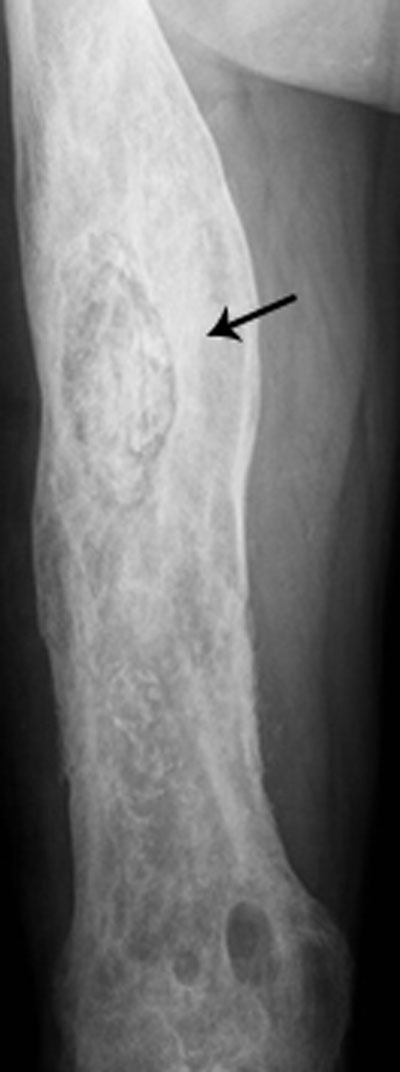

Figure 11

Chronic osteomyelitis on plain radiograph of the femur. Plain radiograph shows diffuse inhomogeneous osteosclerosis of the right femur with a focal area of increased opacity representing necrotic bone or sequestrum (black arrow). Plain films are often difficult to interpret because of superposition of viable and necrotic bone each with a different radiopacity.

Inhomogeneous osteosclerosis and/or sequestrum formation (necrotic bone) is characteristic for chronic osteomyelitis on plain radiography. A sequestrum represents a segment of necrotic bone that is separated from the living bone by granulation tissue and bone resorption. It is typically denser than the living bone [13]. In some cases, a layer of new periosteal bone or involucrum is formed around the necrotic bone (Figures 7, 11, 12). On MRI, a sequestrum is hypo-intense on all pulse sequences. Gadolinium contrast administration may reveal a cloaca (opening in the involucrum) through which pus, granulation tissue and sequestra can be discharged. In addition, enhancement of sinus tracts tracking from the bone to the skin surface is well demonstrated on contrast enhanced MRI (Figure 13) [15].